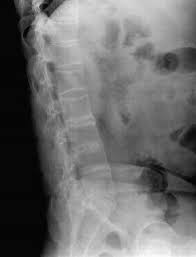

强直性脊柱炎的早期症状比较隐匿,强直性脊柱炎患者可出现厌食、低热、乏力、消瘦和贫血等全身症状,少数病例可有长期低热和关节痛,酷似风湿热表现,个别情况以高热、外周关节等急性炎症表现。强直性脊柱炎患者多为年龄较轻者,以男性患者多见,常伴有消瘦、盗汗等强直性脊柱炎的早期症状。》》》百看不如一问,云骨专家在线为你解答疑惑